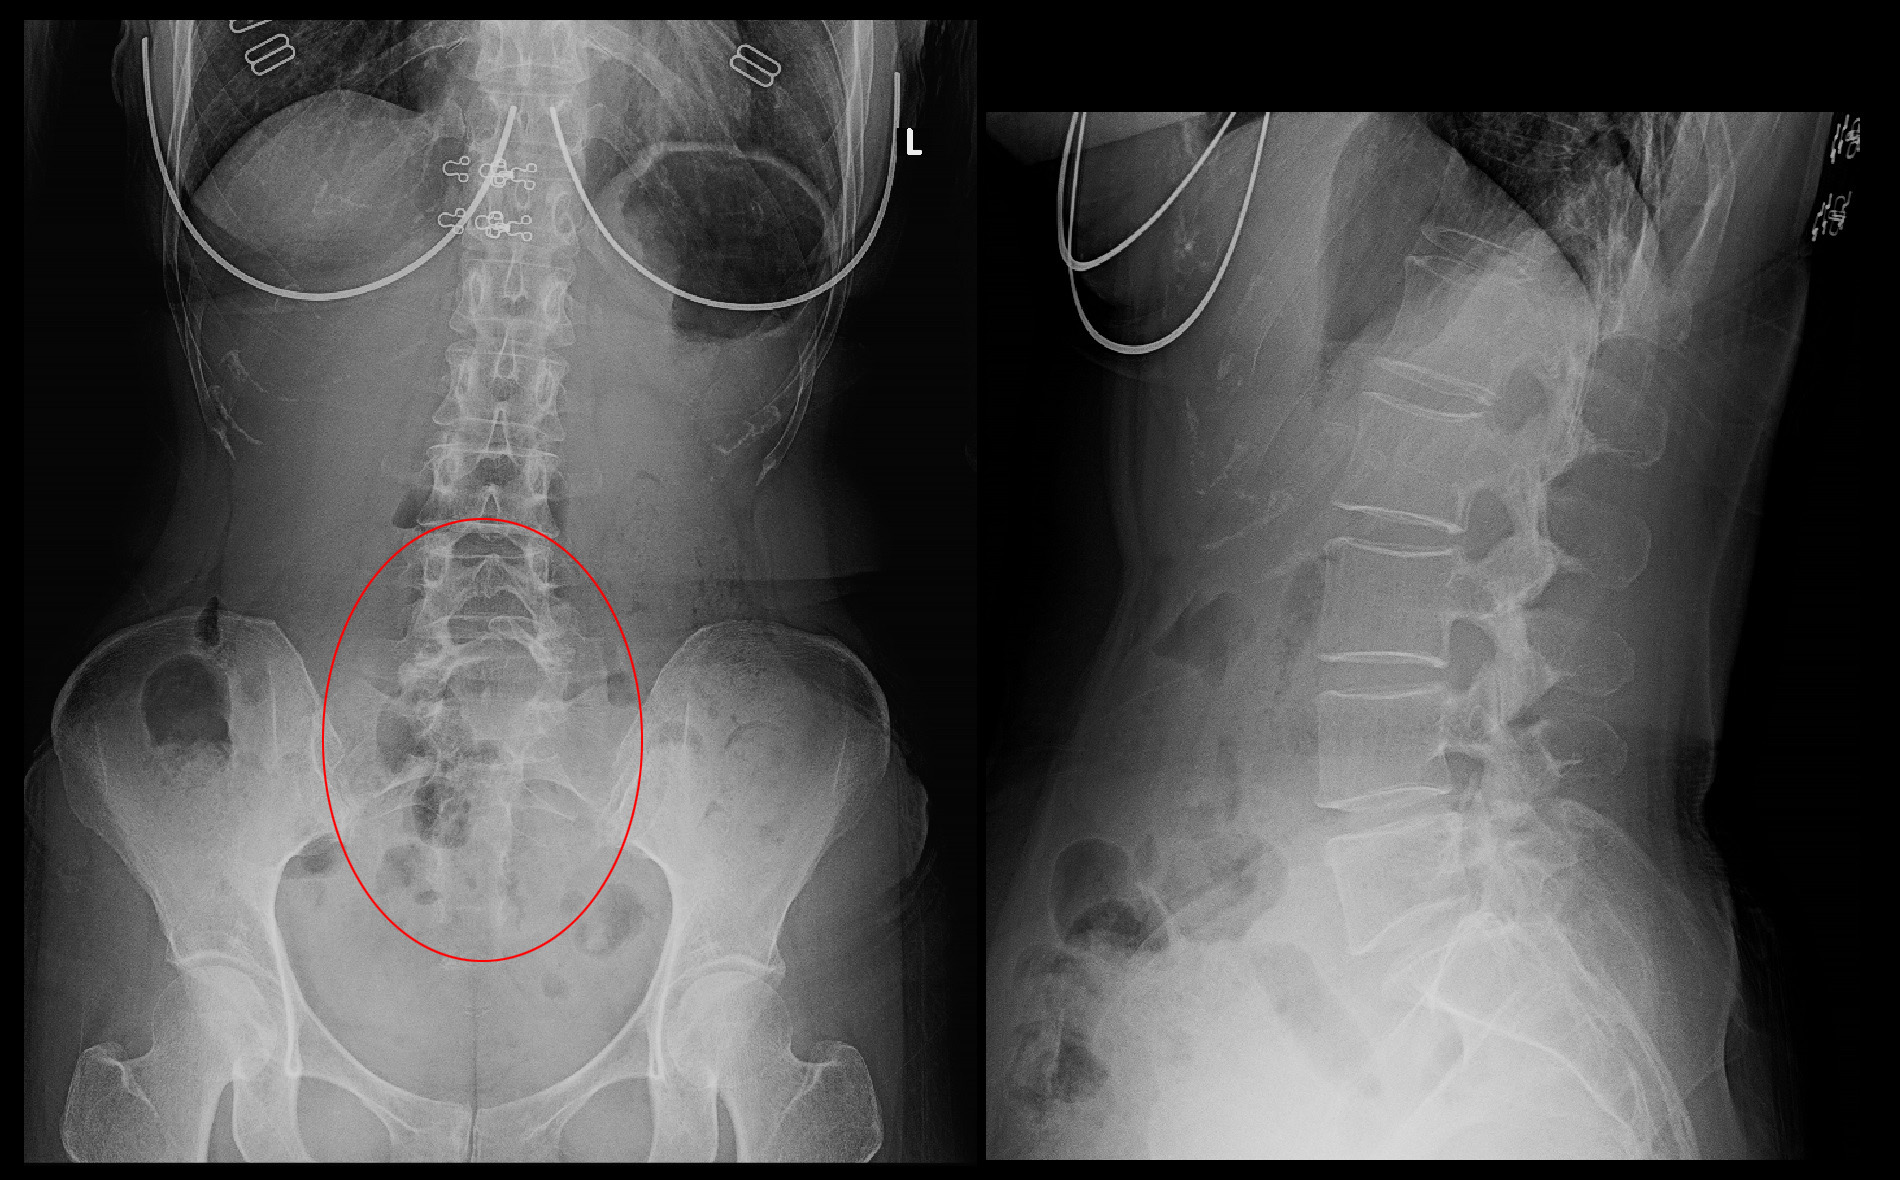

腰椎のレントゲン像ではほとんど異常を認めません。

50才女 Xp2.jpg